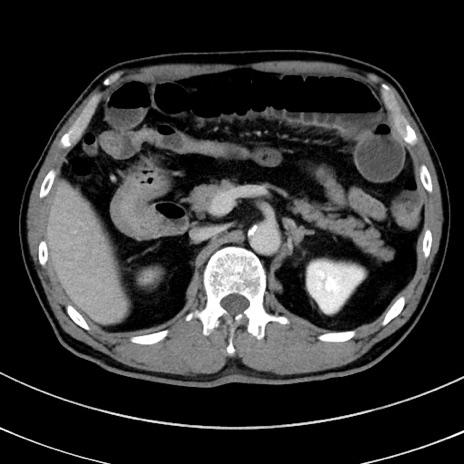

症例

冠状断像